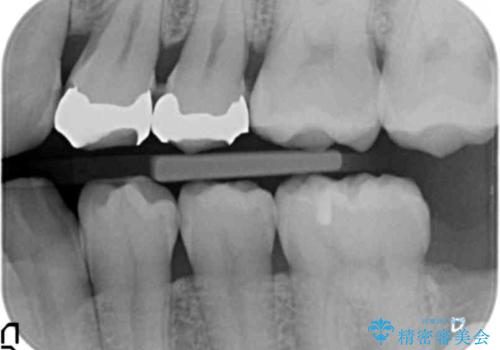

- 近所の歯医者で銀歯を入れたところ噛み合わせも悪く、毎回食べ物が詰まり困るとのことで来院されました。

X線写真より歯と適合の悪い銀歯が装着されていたので、除去し耐久性・削る量の少なくて済むゴールドインレーで再修復を行います。